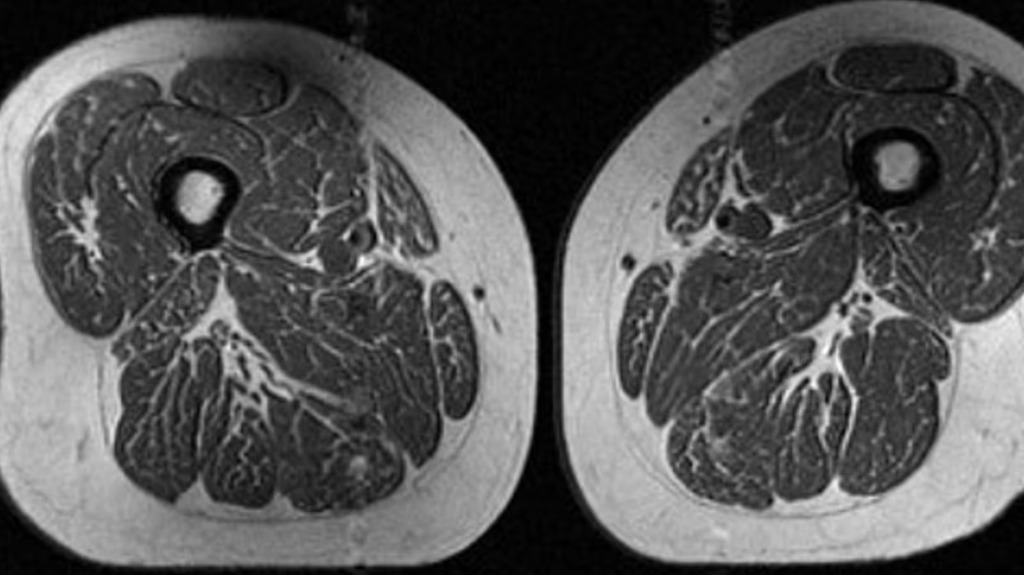

該研究發表在醫學期刊 Radiological Society of North America 旗下期刊《Radiology》上。研究人員通過核磁共振成像(MRI)分析發現,一名62歲女性的大腿肌肉中布滿細密脂肪紋理,而其年度熱量攝入中約87%來自超加工食品。

分析顯示,即使在尚未出現膝關節骨關節炎症狀的人群中,肌肉質量下降的跡象已提前出現。另一名攝入約29%超加工食品的女性,其肌肉脂肪沉積明顯較少。